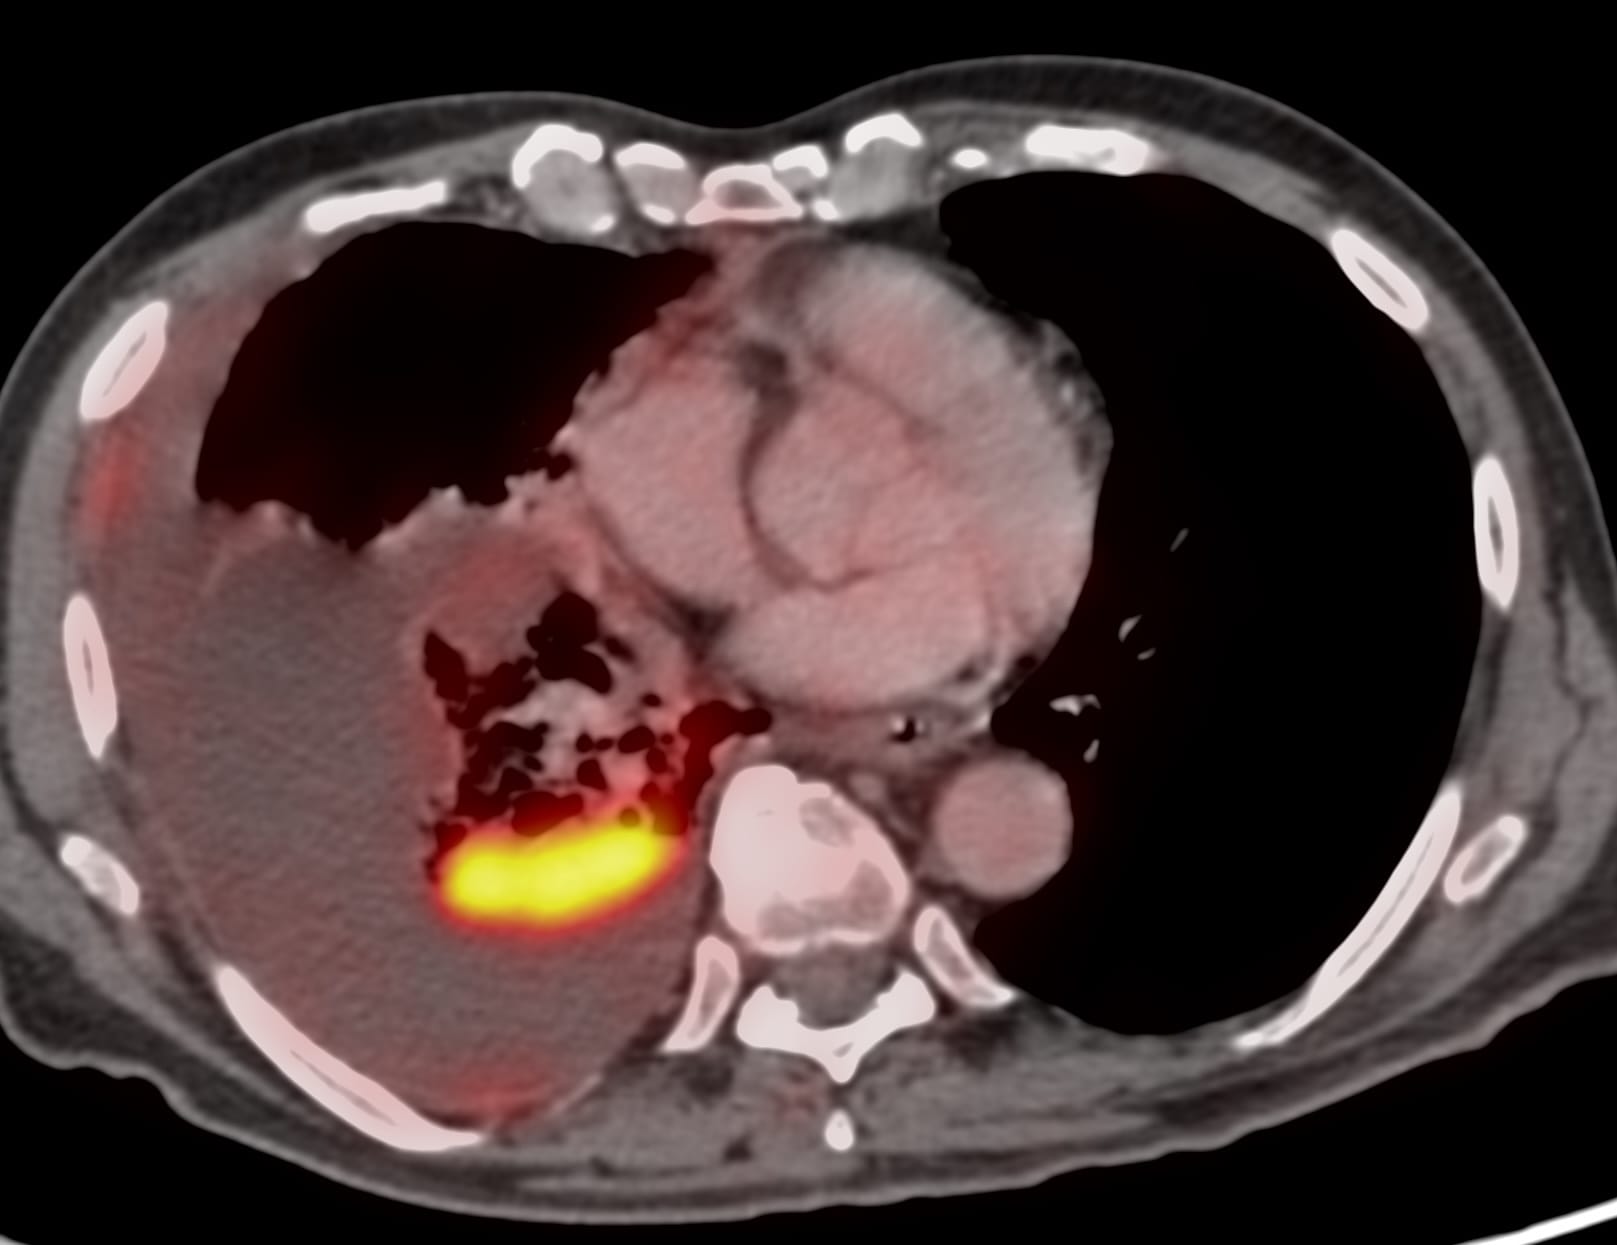

Case 15: 71-years old 40-plus pack years history smoker with non-resolving pleural effusion and an opacity in the right lower lobe